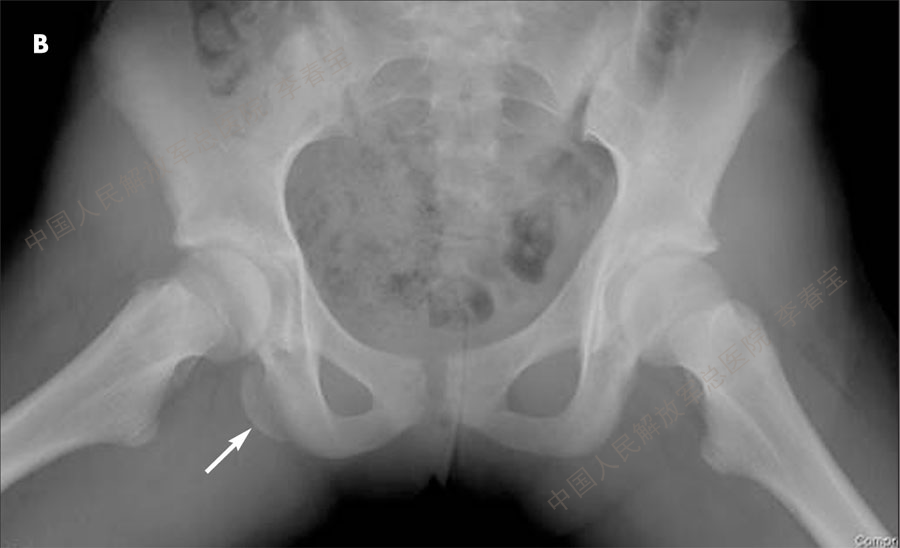

7. 股骨颈骨折

股骨颈骨折根据骨折线的位置分为四型:头下型、经颈型、临床表现;髋关节肿胀、畸形、活动受限、下肢短缩内旋畸形。X片可以确定诊断。治疗:多需要手术治疗。